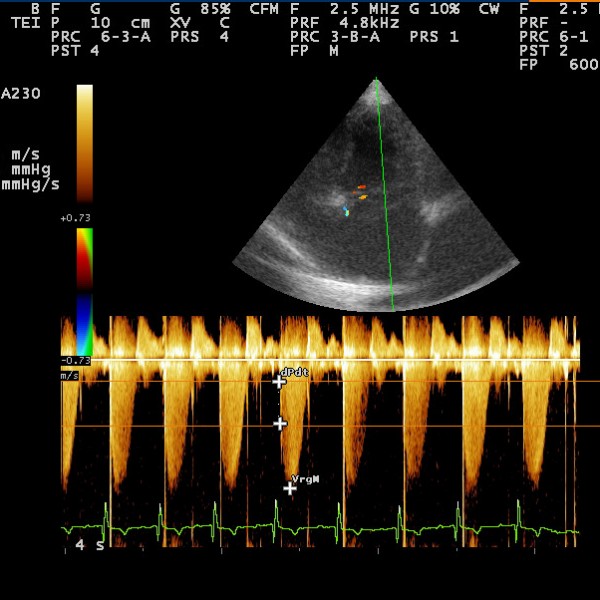

Ecocardiografía Doppler